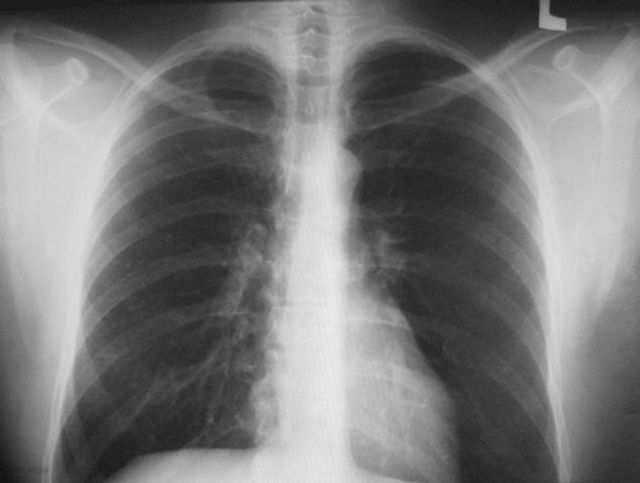

В Копейске не работают два аппарата для проведения исследований на пневмонию. Пациентов временно направляют в другие больницы.

Флюорографические кабинеты закрыты в поликлиниках города Копейска по улице Борьбы и Гастелло. Это связано с выходом из строя оборудования, объяснили в ГКБ № 1.

«Проведение флюорографического обследования с профилактической целью ввиду неисправности оборудования временно приостановлено!» — говорится в сообщении на сайте горбольницы.

«Вся необходимая медицинская помощь оказывается пациентам», — прокомментировали в пресс-службе министерства здравоохранения Челябинской области и уточнили, что в Копейске есть не один флюорограф.